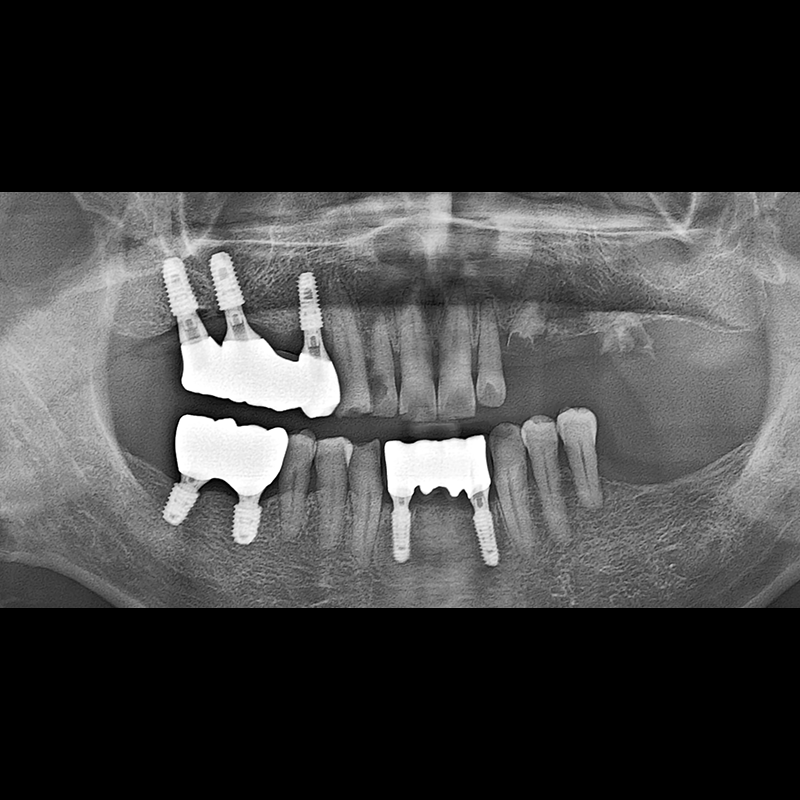

BEFORE AFTER

Implant before and after 2025.05.30

Implants were placed in the missing tooth and in the tooth position where it was difficult to save.